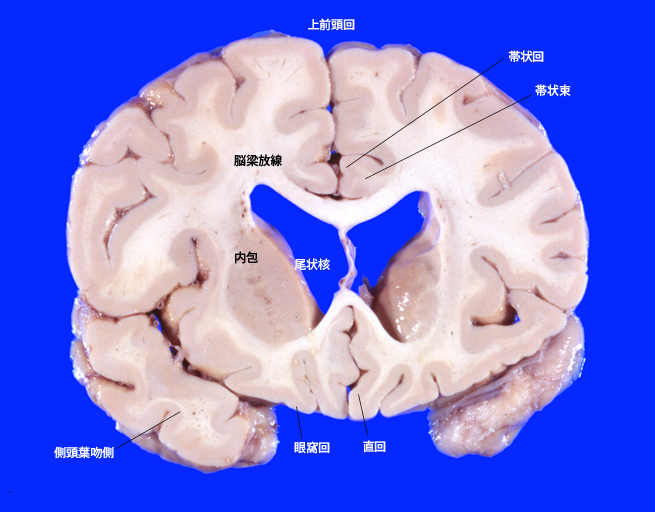

脳前頭断面の解剖*1

1. 基準前頭断面(乳頭体をとおるラインでの割面)

7. 線状体(尾状核+被殻)頭部をとおる前頭断面

8. 側頭葉極、尾状核頭の前頭断面